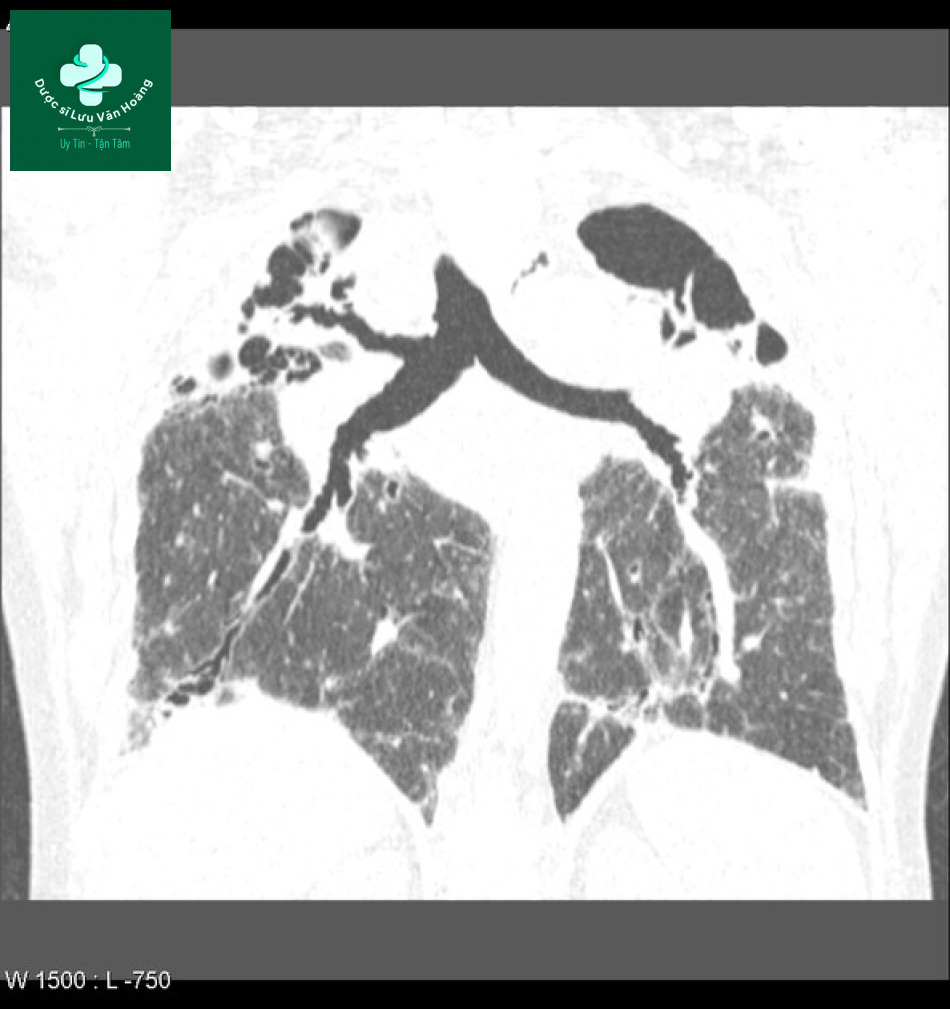

Case 2: giai đoạn II.

- Phim x-quang cho thấy tổn thương dạng lưới nốt ở vùng trên phổi với hạch rốn phổi và trung thất, phù hợp với giai đoạn II.

- CT cho thấy tổn thương dạng nốt lan tỏa phân bố quanh phế quản và đông đặc ở thùy trên. Một số có hình kính mờ xung quanh. Không có tổn thương xơ hóa.

- Sau 3 năm điều trị thì tổn thương đã giảm rõ rệt.